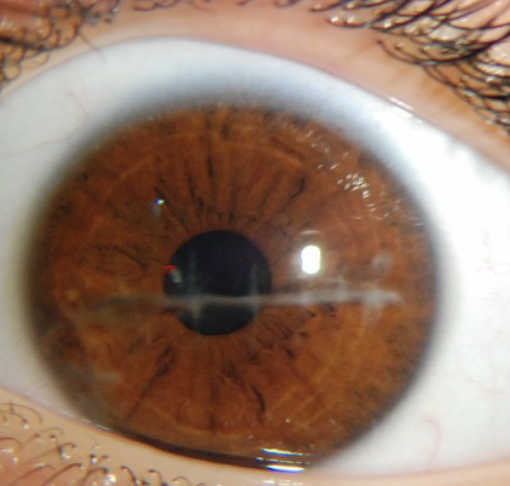

Keratoconus

One of the 6 Corneal Abnormalities

A progressive, degenerative disorder where the cornea thins and bulges into a cone shape, leading to distorted vision